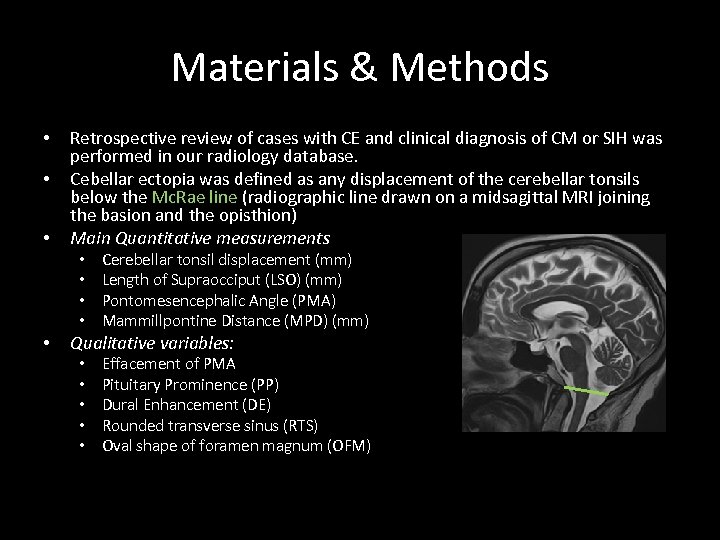

Materials & Methods • • • Retrospective review of cases with CE and clinical diagnosis of CM or SIH was performed in our radiology database. Cebellar ectopia was defined as any displacement of the cerebellar tonsils below the Mc. Rae line (radiographic line drawn on a midsagittal MRI joining the basion and the opisthion) Main Quantitative measurements • • • Cerebellar tonsil displacement (mm) Length of Supraocciput (LSO) (mm) Pontomesencephalic Angle (PMA) Mammillpontine Distance (MPD) (mm) Qualitative variables: • • • Effacement of PMA Pituitary Prominence (PP) Dural Enhancement (DE) Rounded transverse sinus (RTS) Oval shape of foramen magnum (OFM)

Materials & Methods • • • Retrospective review of cases with CE and clinical diagnosis of CM or SIH was performed in our radiology database. Cebellar ectopia was defined as any displacement of the cerebellar tonsils below the Mc. Rae line (radiographic line drawn on a midsagittal MRI joining the basion and the opisthion) Main Quantitative measurements • • • Cerebellar tonsil displacement (mm) Length of Supraocciput (LSO) (mm) Pontomesencephalic Angle (PMA) Mammillpontine Distance (MPD) (mm) Qualitative variables: • • • Effacement of PMA Pituitary Prominence (PP) Dural Enhancement (DE) Rounded transverse sinus (RTS) Oval shape of foramen magnum (OFM)

Materials & Methods • SPSS was used for statistical analysis; t-test and exact test were used for quantitative and qualitative differences between groups, respectively. • 63 cases of CM and 23 cases of SIH were selected.

Materials & Methods • SPSS was used for statistical analysis; t-test and exact test were used for quantitative and qualitative differences between groups, respectively. • 63 cases of CM and 23 cases of SIH were selected.